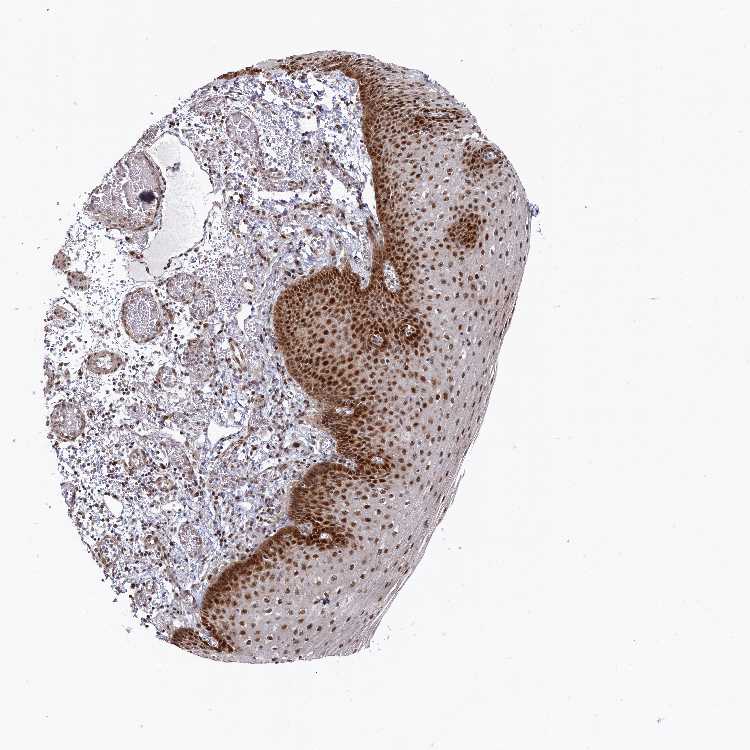

ESOPHAGUS - Antibody stainingi

Antibody staining in the annotated cell types in the current human tissue is reported as not detected, low, medium, or high, based on conventional immunohistochemistry profiling in selected tissues. This score is based on the combination of the staining intensity and fraction of stained cells.

Each image is clickable and will lead to virtual microscopy that enables deeper exploration of all samples and also displays staining intensity scores, fraction scores and subcellular localization as well as patient and tissue information for each sample.

Antibody HPA003601Antibody CAB037075

Squamous epithelial cells MediumHigh